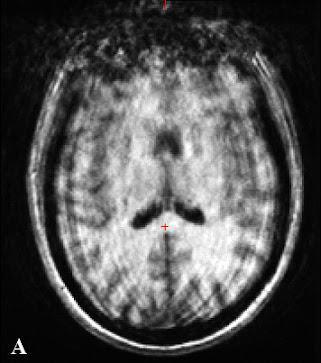

dEEGtal est un logiciel alimenté par l’IA qui améliore la détection précoce de l'épilepsie en analysant les données EEG avec précision, fournissant des informations rapides et fiables, dès la première crise

Possible première crise d’épilepsie

dEEGtal répond à un besoin crucial dans le diagnostic de l'épilepsie. Après un premier épisode ressemblant à une crise, les patients reçoivent une neuroimagerie et un électroencéphalogramme (EEG) Malgré le fait que ces examens soient les meilleurs outils disponibles, un patient sur deux quitte les urgences sans diagnostic L'EEG, bien que très spécifique, manque de sensibilité, en particulier après une première crise Ainsi, 70 à 80 % des EEG sont jugés normaux après une interprétation visuelle, ne permettant pas d'établir un diagnostic. Sans diagnostic clair, aucun traitement ne peut être initié, exposant les patients à un risque de nouvelle crise dans 70 % des cas, avec des conséquences sociales et psychologiques importantes dEEGtal utilise l'intelligence artificielle pour améliorer la sensibilité de l'interprétation des EEG, permettant un diagnostic plus précoce et précis, facilitant ainsi un traitement rapide et améliorant le pronostic des patients

dEEGtal, contrairement aux solutions présentes sur le marché, fournit un score de risque d’épilepsie, facilite l’interprétation en proposant une interprétation automatisée des périodes de ralentissement visibles sur le signal et génère des rapports automatiques, tout en résumant les informations essentielles à l’interprétation de l’EEG dEEGtal, agit ainsi comme un copilote, assistant le neurologue dans sa lecture du tracé L’interface intuitive et personnalisable permet une intégration fluide dans le travail des cliniciens au quotidien, tout en offrant des outils avancés pour comparer les EEG dans le temps et suivre l’évolution des patients.

Les premiers résultats de notre modèle de réseau de neurones convolutifs (CNN) sont prometteurs Sur un ensemble de données composé de 1’500 patients, notre prototype a atteint une sensibilité de 65 % et une spécificité de 90 %, soit plus du double des capacités diagnostiques de la méthode actuelle. Ces résultats devront être confirmés sur des ensembles de données plus divers provenant de centres nationaux et internationaux pour assurer la généralisation de l'algorithme avant d’obtenir les marquages CE et FDA faisant de dEEGtal un dispositif médical. Ceci mènera dEEGtal à une mise sur le marché prévue pour 2028